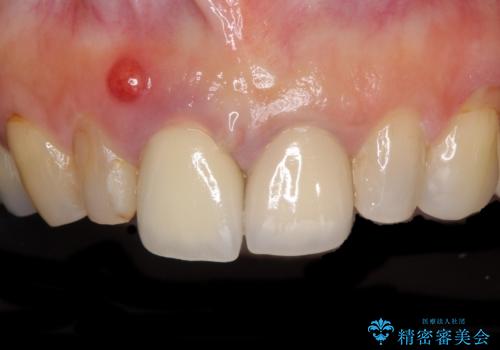

度重なる治療で前歯がしみる オールセラミッククラウンによる補綴治療